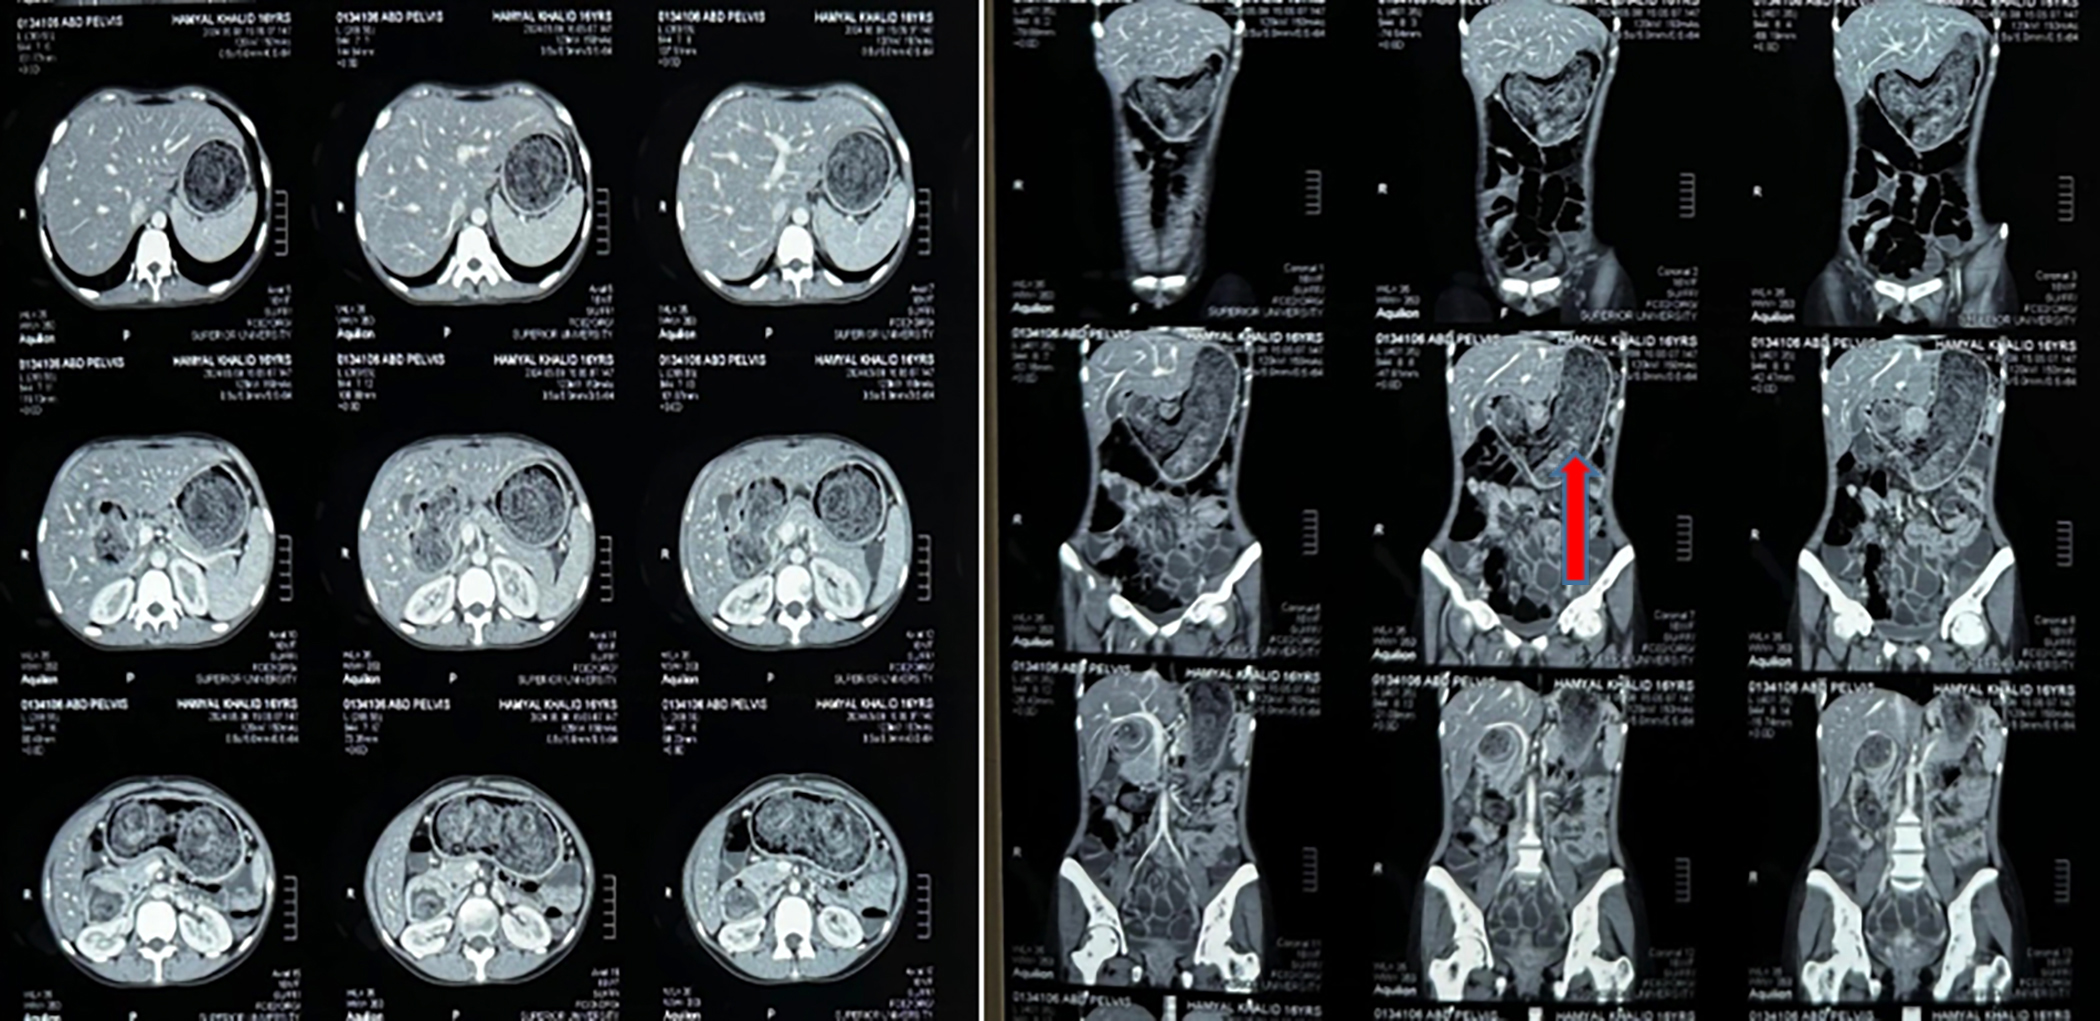

Physical examination showed a cachexic female patient with a body mass index (BMI) of 15 kg/m2 and normal vital signs. The abdominal examination showed a distended abdomen without any tenderness or signs of peritonitis or palpable abdominal mass. The chest x-ray was normal. Abdominal x-ray showed a distended stomach with displaced small gut loops. The abdominal ultrasound report showed a distended stomach with collapsed distal gut loops. Computer tomography (CT) revealed intestinal obstruction at the level of the ileum with distended proximal stomach and duodenum and suspicion of bezoar and jejunoileal intussusception (Figure 1). The diagnosis of intestinal obstruction due to bezoar and intussusception was made. A plan of exploratory laparotomy under general anaesthesia after taking informed and written consent from the family of the patient was finalised.

Figure 1: Axial and coronal views of CT scan of the abdomen showing a mass completely filling the stomach and extending into duodenum and jejunum (red arrows).